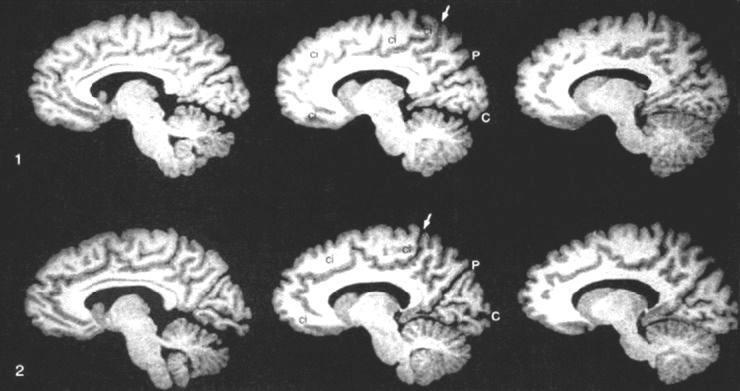

MRI-скан мозга однояйцевых близнецов. Между P и стрелкой у ребенка в верхнем ряду 3 мозговые извилины, а у ребенка в нижнем ряду 4 (Steinmetz H., Herzog A., Huang Y., Hacklander T. Discordant Brain-Surface Anatomy in Monozygotic Twins // The New England Journal of Medicine. 1994.  331. P. 951952). Паттерн мозговых извилин и борозд формируется главным образом в течение трех последних месяцев беременности. Таким образом, причина этих негенетических различий должна возникать именно в этот период.